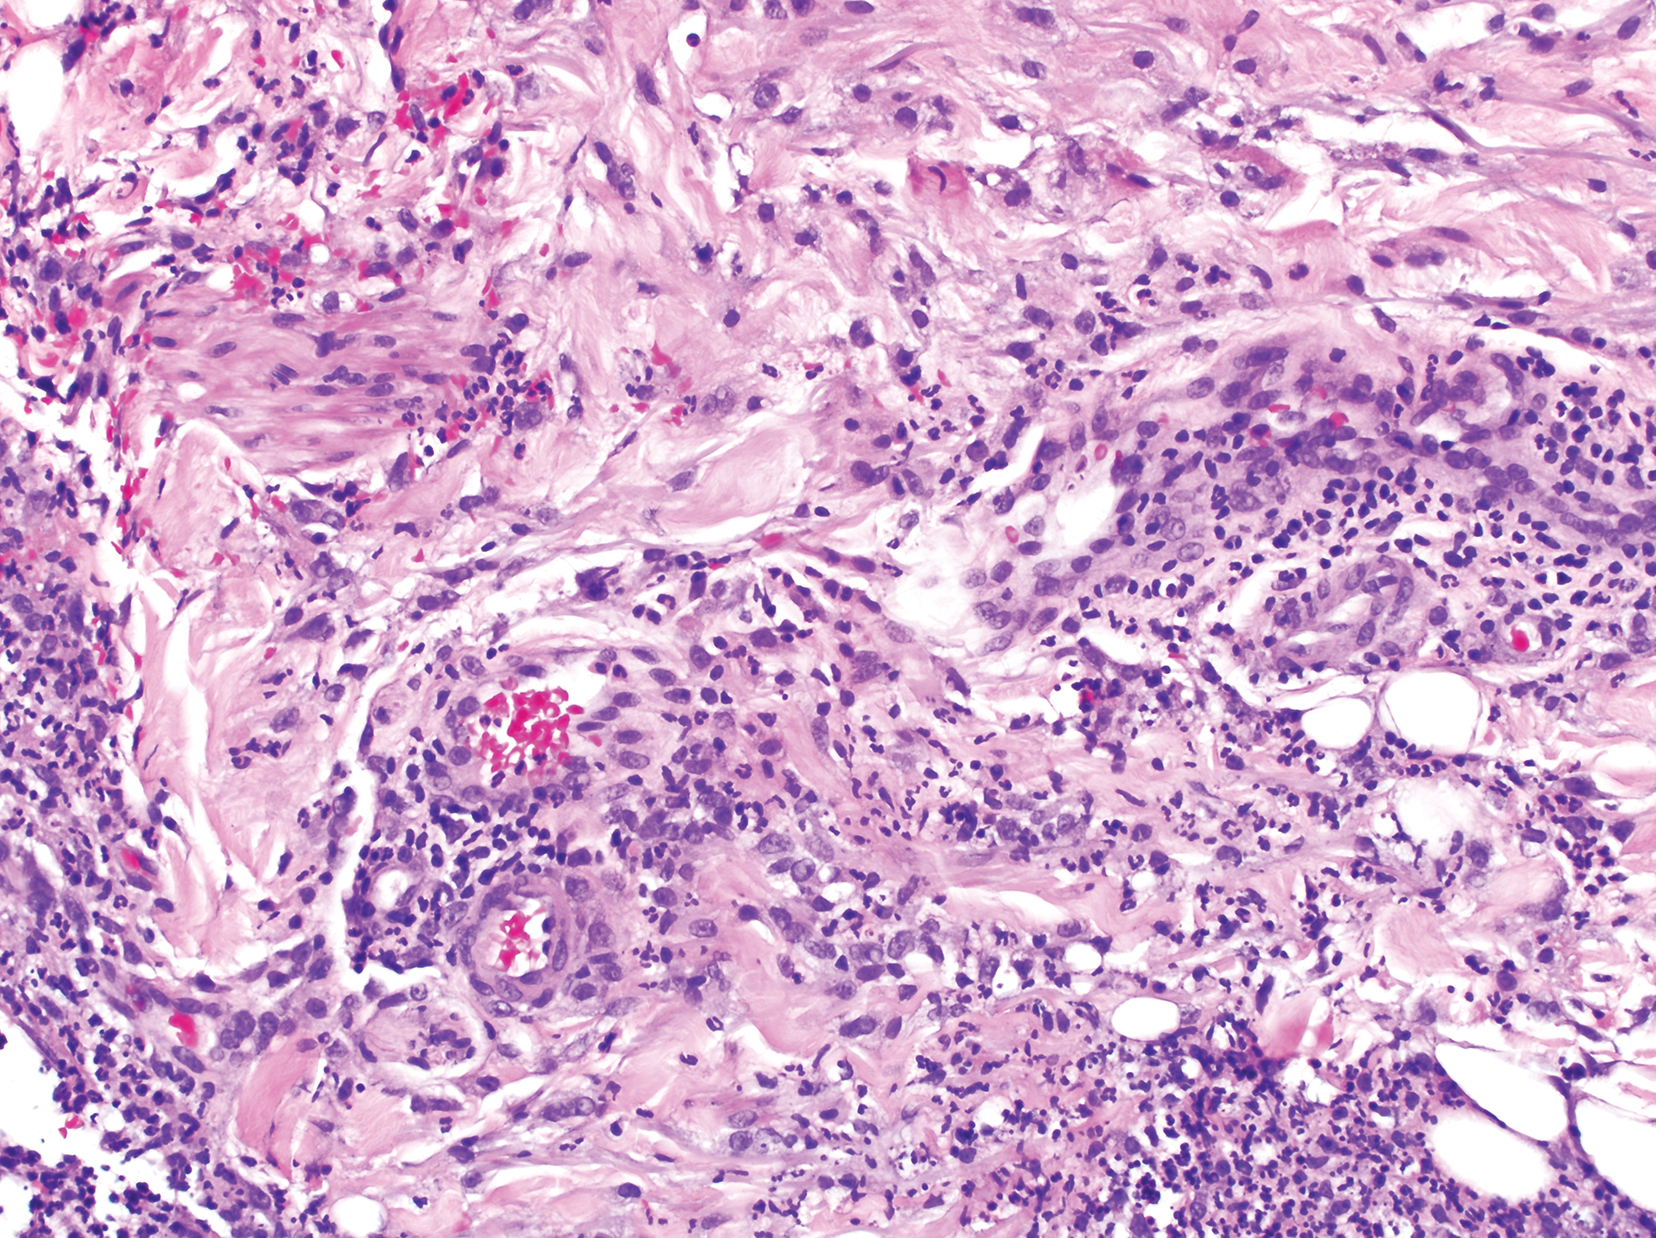

Computed tomography of the head revealed a 14-mm, ring-enhancing lesion in the left paramedian posterior frontal lobe with surrounding white matter vasogenic edema (Figure 1). Computed tomography of the chest revealed a peripheral mass on the right upper lobe measuring 6.3 cm at its greatest dimension (Figure 2).

Figure 1. Computed tomography of the head showed a 14-mm, ring-enhancing lesion in the left paramedian posterior frontal lobe with surrounding white matter vasogenic edema (red circle).